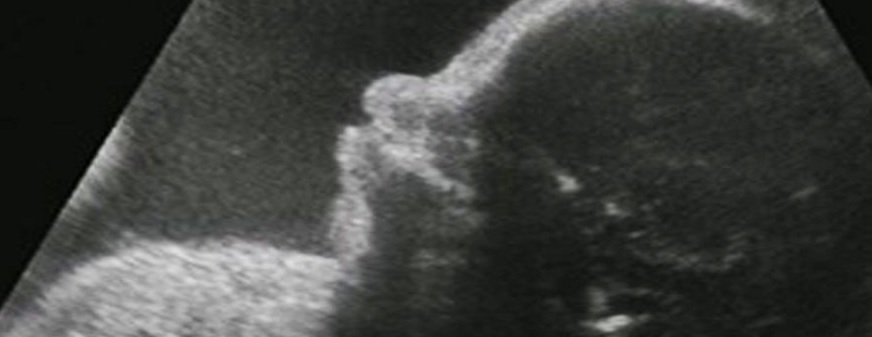

But, at the time, we didn’t have much understanding of what abortion was. We knew nothing of fetal development. We consistently termed the fetus “a blob of tissue,” and that’s just how we pictured it — an undifferentiated mucous-like blob, not recognizable as human or even as alive. It would be another 15 years of so before pregnant couples could show off sonograms of their unborn babies, shocking us with the obvious humanity of the unborn.

In time, it’s going to be impossible to deny that abortion is violence against children. Future generations, as they look back, are not necessarily going to go easy on ours. Our bland acceptance of abortion is not going to look like an understandable goof. In fact, the kind of hatred that people now level at Nazis and slave-owners may well fall upon our era. Future generations can accurately say, “It’s not like they didn’t know.” They can say, “After all, they had sonograms.” They may consider this bloodshed to be a form of genocide. They might judge our generation to be monsters.